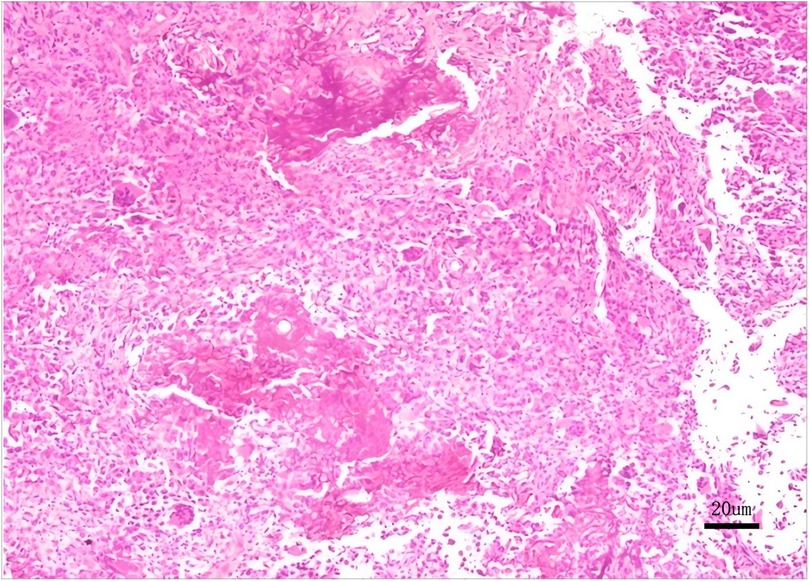

Microscopic image showing a cluster of cells stained in shades of pink, displaying a dense and varied texture. A 20 micrometer scale bar is present at the bottom right, indicating the scale of magnification.

Figure 4. Histopathological biopsy reveals a proliferation of round to oval cells with scattered osteoclast-like multinucleated giant cells and characteristic chondroid matrix calcification, immunohistochemical findings certified chondroblastoma.